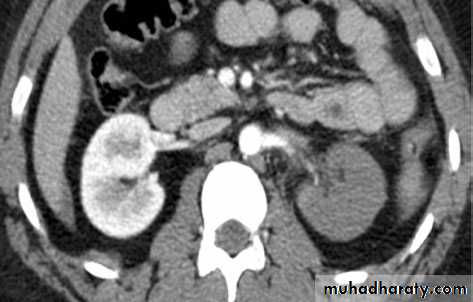

10Renal CT with IV contrast in blunt trauma patent shows a

superfi cial (grade 2) laceration amenable to nonoperative management.

Treatment

Conservative (nonoperative) management::::

• Most blunt (95%) and many penetrating renal injuries (50% of stab injuries and 25% of gunshot wounds) can be managed nonoperatively.